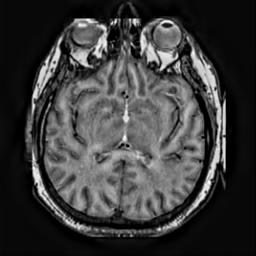

To demonstrate the effectiveness and efficiency of the proposed image fusion method , we conduct a set of comparative experiments on three image datasets. The first is composed by 8 pairs of multi-modal medical images and the second one contains 15 pairs of multi-focus gray or color natural images. These two datasets are often used in many related papers and some examples are shown in Figure 3(a) and Figure 3(b). The third one is a new multi-focus cervical cell image dataset collected by ourselves, which consists of 15 groups of color images and each group contains a series of multi-focus cervix cell images with size of or , etc. Some source examples are shown in Figure 3(c). Our source code implemented in C++ along with the new multi-focus cervical cell image dataset is available online.

We first evaluate the performance of the proposed method under varying total number of octaves and number of layers sampled per octave. The fused images of a pair of multi-modal medical images with different and are shown in Figure 4. In this example, on the one hand, when only 1 or 2 octaves are involved in constructing the DoG pyramid, the fused images fail to keep the integrity information of large size objects (e.g. eyeballs), while by increasing the value of , the integrity information of eyeballs is preserved. On the other hand, although not as significant as the increase of octave numbers , the fused image can contain more details by the increase of layer numbers . The corresponding objective quality metrics are shown in Figure 5. As shown in Figure 5(a), most of the metric values are improved as the number of octaves increases with the fixed layer numbers 3 in the global tendency and each of them tends to be stable when the number of octaves is 5. To get a relatively good quality from Figure 5(b), we can notice that some of the metric values can get a good performance when the number of layers is 3, such as the MI, SSIM, QI and VIF, though there are only a little change of all the metric values by increasing the number of layers with the fixed octave numbers 5. Because it will result in more computation burden with the increase of the value and , and for different kinds of source images, there are different performance with the diverse parameter settings. To get a trade-off between them in our experiments, we set for the multi-modal dataset, for the natural datasets and for the multi-focus cell dataset, respectively.

Figure 6 shows the fused images obtained by different methods with the multi-modal source images shown in Figure 3(a). As shown in these figures, the proposed method can produce images which preserve the complementary information of different source images well. Moreover, due to the scale-invariant structure saliency selection, our method can keep the integrity information of large size objects and the visual details simultaneously. Although the fused image generated by other methods can also capture the details to some extent, all of them fail to keep the integrity information of large size objects such as the eyeballs. Furthermore, from Figure 6(k)-6(t), the DTCWT, GFF, IM and NSCT methods may decrease the brightness and contrast while the proposed method can preserve these features and details without producing visible artifacts and brightness distortions.